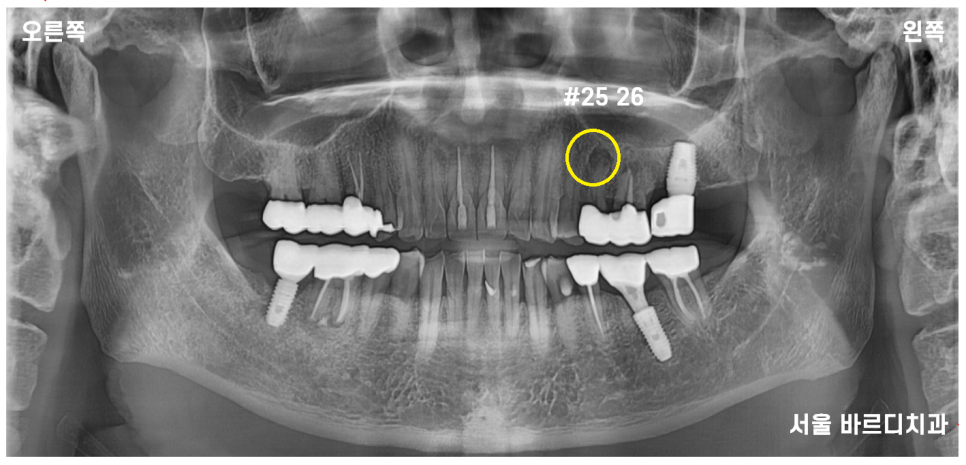

23.07.06

전반적으로 잇몸이 조금씩 내려간 부분은 있었지만

제일 문제가 되는 부분은 왼쪽 위였습니다.

파노라마 전체 사진상으로도

좋아 보이지 않아

자세히 관찰할 수 있는

작은 x-ray를 한 장 더 찍어 보았습니다.

노랗게 동그라미 친 부분이

치아 뿌리 끝에 염증을 의미합니다.

이미 치료를 받은 치아에 염증이 생겨

주변 뼈를 녹이고 있는 상태

옆에 치아도 좋지 않은 것은 마찬가지였습니다.